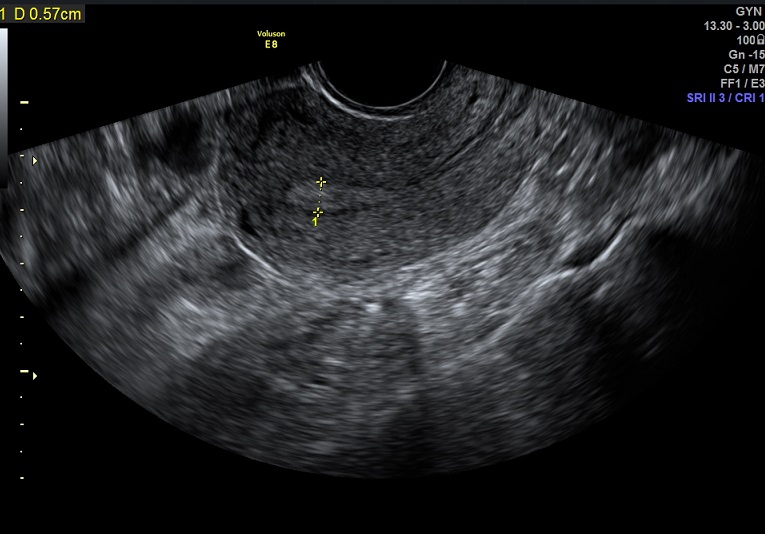

| 女性,25岁,继发性不孕1年余,难免流产4次。 | ||

2015-1-26 月经第23天检查 黄体期 |

2015-1-26图示